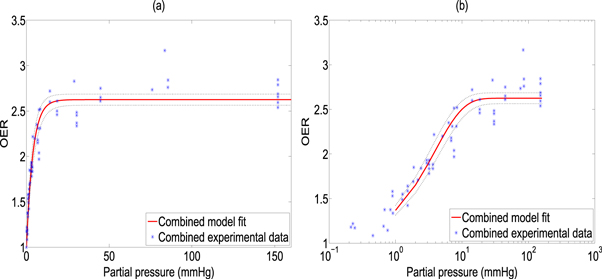

The model was fitted to the experimental data and goodness of fit calculated and 95% confidence intervals using a nonlinear least squares algorithm, illustrated in figure 2. All points were then pooled and the same analysis was performed, illustrated in figure 3. Results and estimated values are shown in table 4, yielding good fits to experimental data.

Standard image High-resolution imageFigure 3. Model fit from combined data sets shown with (a) standard x-axis (b) logarithmic X-axis for clarity. 95% confidence intervals shown by dotted black lines.

Download figure: